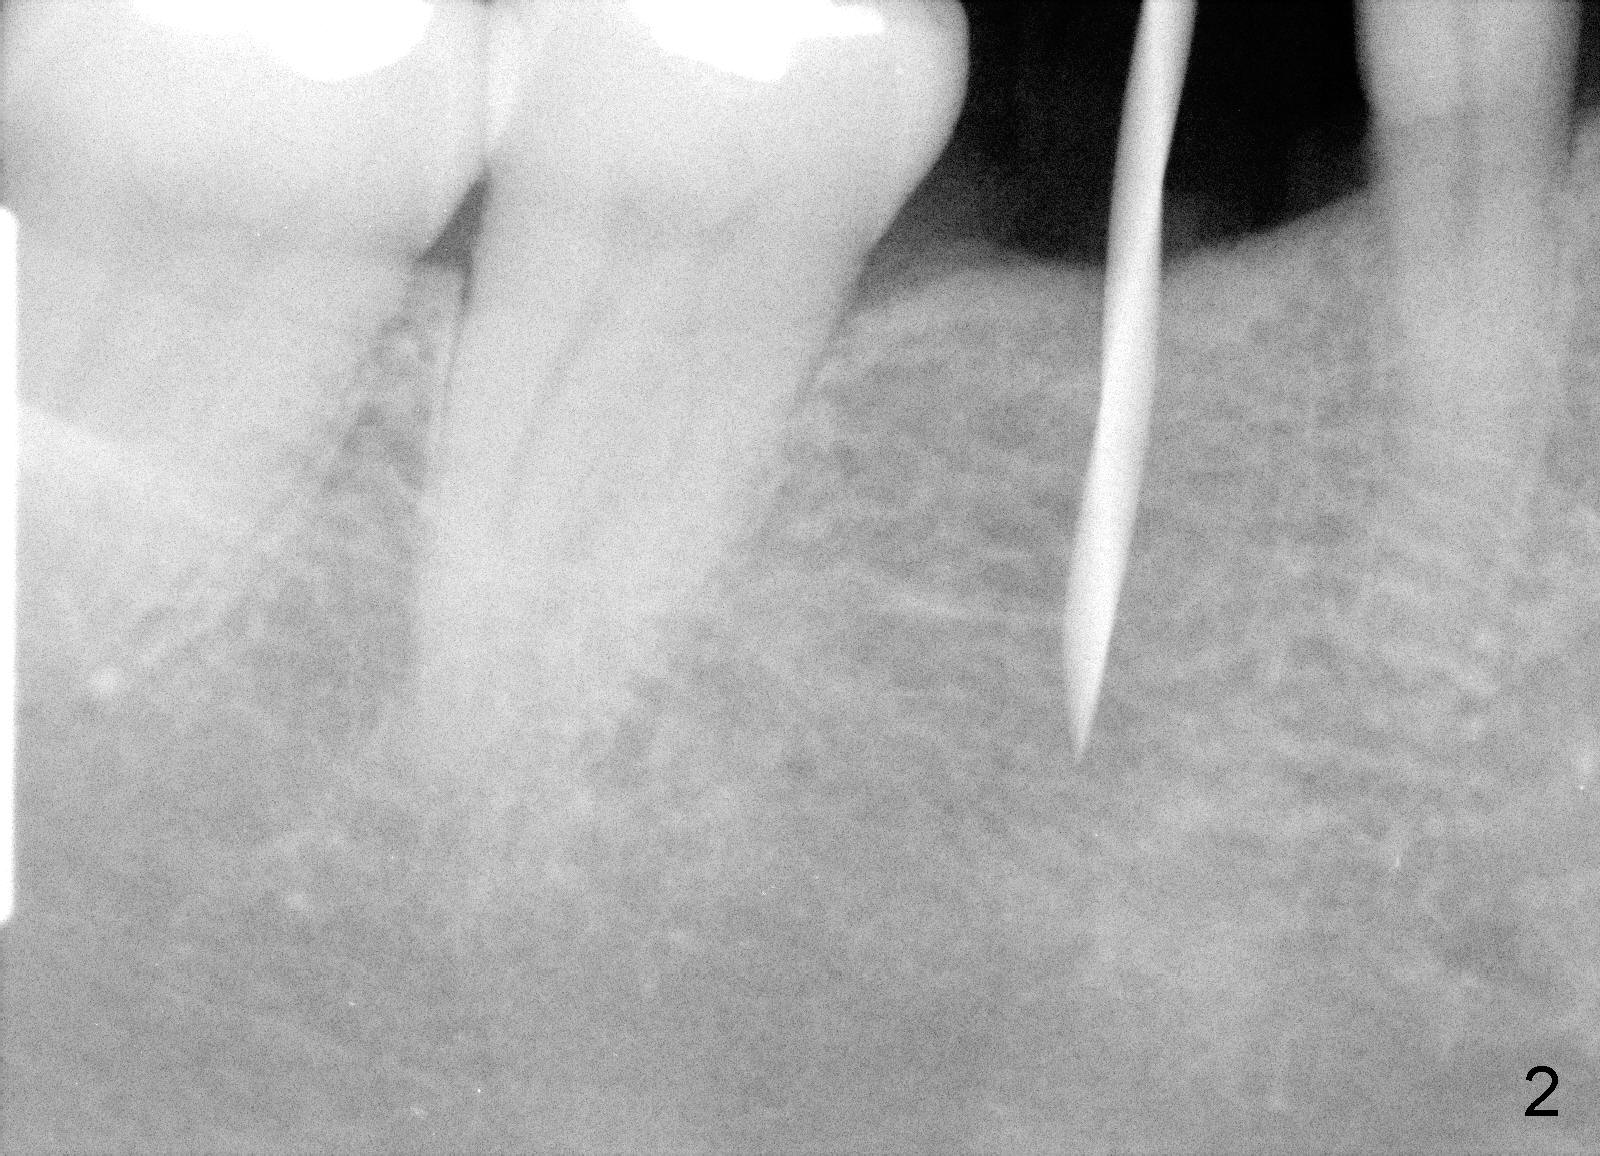

Due to unavailability of bone-level implant, a tissue-level implant is to be placed as a backup (Fig.1: 4.5x17 mm). Osteotomy is initiated with 1.5 mm pilot drill at depth of ~ 10 mm; the trajectory appears to be as good as expected (Fig.2). Osteotomy is gradually increased to 4.5x17 mm, followed by insertion of 4.5x17 mm tap (Fig.3,4). The ostetomy appears to be deviated lingual (Fig.5). When the tap is removed, the buccal plate appears to be thin (Fig.6). A tapered implant is placed (Fig.7).